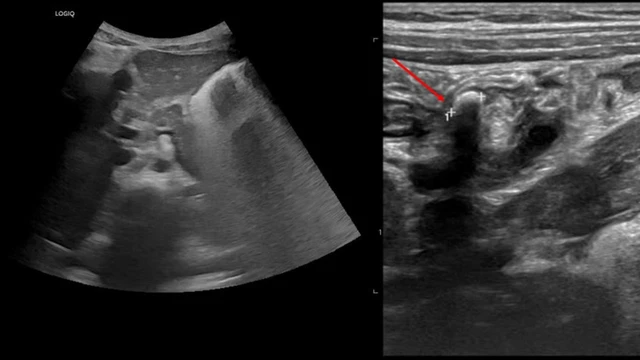

/https://cms-prod.s3-sgn09.fptcloud.com/ket_qua_sieu_am_viem_ruot_thua_0_6b82898c8b.jpg)

Viêm ruột thừa là một tình trạng cấp cứu ngoại khoa phổ biến, đòi hỏi chẩn đoán nhanh chóng và chính xác. Trong đó, kết quả siêu âm viêm ruột thừa đóng vai trò quan trọng trong việc xác định tình trạng viêm và hỗ trợ bác sĩ đưa ra quyết định điều trị kịp thời. Việc hiểu rõ kết quả siêu âm giúp bệnh nhân và người nhà có cái nhìn cụ thể hơn về tình trạng sức khỏe, từ đó có hướng xử lý phù hợp.